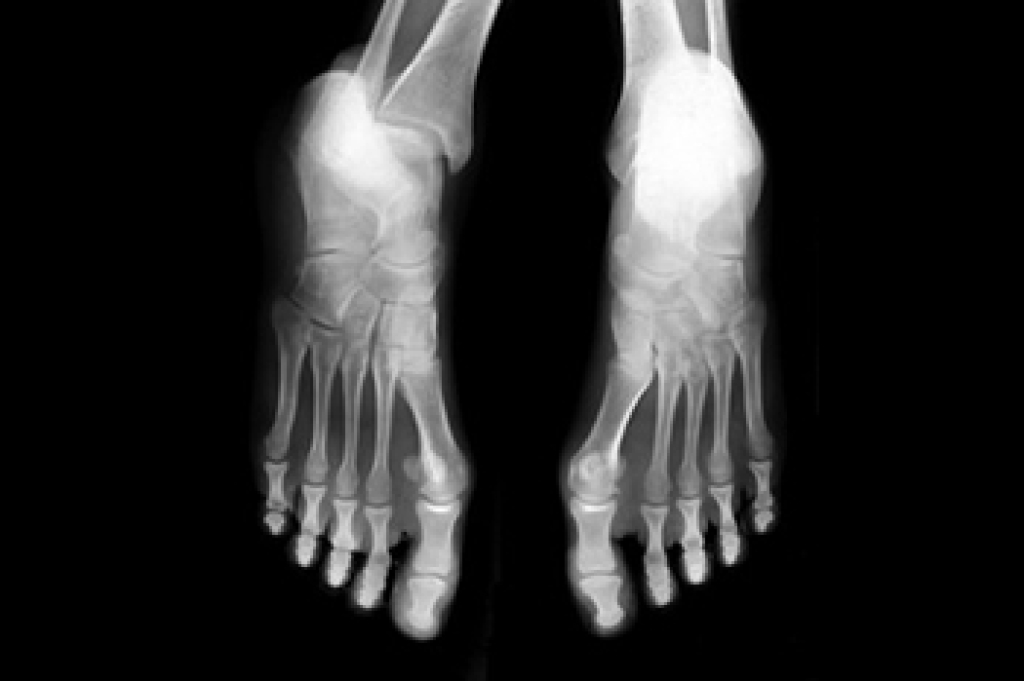

Pregnancy is a transformative journey, both physically and emotionally. While the focus is often on the growing belly and changing hormones, the feet and ankles quietly bear the burden of these changes also. Swollen feet and ankles, a common pregnancy woe, occur due to increased blood volume and pressure on veins, causing fluid retention. This can lead to discomfort and sometimes pain. Additionally, hormonal shifts can affect ligaments, making them more relaxed and prone to injury. As pregnancy progresses, the arches of the feet may flatten, leading to fallen arches or flat feet. These changes can persist even after childbirth. Fortunately, there are ways to alleviate these issues, such as wearing comfortable, supportive shoes, elevating the feet when possible, and staying hydrated. Pregnancy is a beautiful journey, and it is essential to remember that taking care of your feet and ankles is an integral part of the process. If you would like more information about proper foot care during pregnancy, it is suggested that you speak with a podiatrist who can provide you with useful tips.

One problem that can occur is overpronation, which occurs when the arch of the foot flattens and tends to roll inward. This can cause pain and discomfort in your heels while you’re walking or even just standing up, trying to support your baby.

Another problem is edema, or swelling in the extremities. This often affects the feet during pregnancy but tends to occur in the later stages.